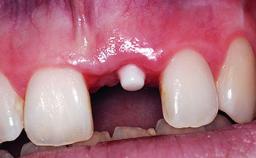

A 32-year-old female Caucasian patient with a compromised maxillary right central incisor was referred to us by a general dentist. Her chief complaints were discomfort and mobility of tooth 11 with unsatisfactory esthetics due to discoloration. The patient reported a previous trauma, some years earlier, as the origin of pathology on the afflicted tooth. Anamnesis was negative for any other dental or periodontal pathology in the remaining dentition. The patient did not take any medication and reported to be a light smoker (5–10 cigs/day). She had high esthetic expectations of her treatment. The extraoral examination revealed a high smile line with full exposure of her maxillary teeth and surrounding soft tissue in the area between the second premolars.

Bone Augmentation Horizontal|Simultaneous|Staged

Soft Tissue Grafting Staged